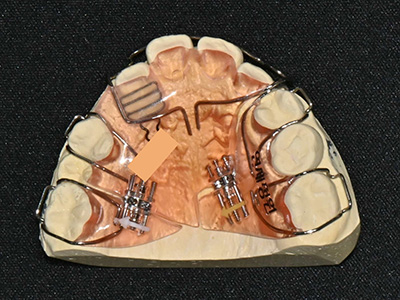

치과대학에서 원내생 실습을 하는 동안 가철성 교정장치를 만드는 실습을 하는데, 그 때 점수도 가장 높고 가장 만들기 어려운 장치가 하나 있었는데요... 바로 이런 케이스를 교정해주기 위한 "sagittal appliance" 입니다. 이 장치의 역할은 송곳니가 맹출할 수 있는 공간을 확보하기 위해 앞니는 앞으로 밀어주고, 어금니는 뒤로 밀어주는 장치입니다.

위 환자의 경우 안으로 들어와있는 앞니도 밀어주고 공간이 부족해서 나오지 못하고 있는 작은 어금니 공간도 마련해주기 위해 sagittal appliance에 앞니를 밀어주기 위한 push spring과 작은 어금니 공간을 마련해주기 위한 distal screw도 추가해주었습니다. 이 정도면 10점짜리 최고난이도 장치가 아닐까 싶습니다 ^^;;

Sagittal appliance with distal screw and push spring